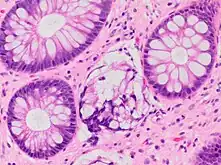

Paneth cell (pictured) or gastric metaplasia (only applies in the left colon and rectum)

Other findings include basal plasmacytosis and mucin depletion.[4] Histopathology findings generally associated with active colitis include:[4]